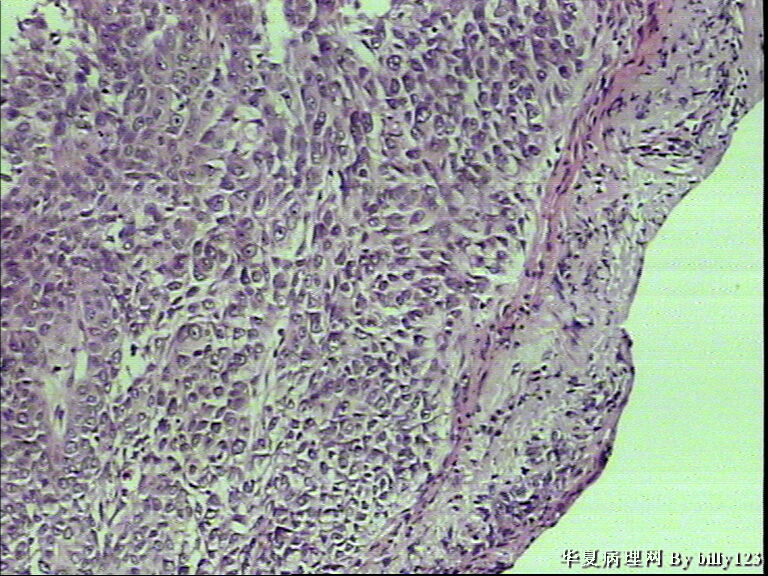

支气管活检,患者,男性,66岁,支气管镜下见息肉样新生物,鳞癌吗?请各位老师指教!

• 支气管活检,患者,男性,66岁,支气管镜下见息肉样新生物,鳞癌吗?请各位老师指教!图1

鳞状上皮不典型增生,炎症明显,还不能诊断癌,建议密切随访观察。

全层有不典型增生 有坏死 考虑鳞癌

鳞状上皮重度不典型增生,局部疑为癌

如果全面观察过切片确实没有浸润,可诊断为原位鳞癌。

鳞状上皮重度不典型增生,局部可疑浸润。

从第二,三张图片的组织结构是鳞癌

棘层松解型鳞癌